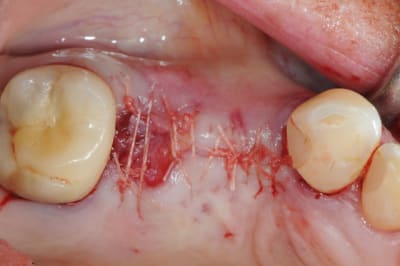

un petit exemple de ce matin: extraction des piliers 12 et 14, curetage, comblement avec du bio-oss de la dépression osseuse vestibulaire au niveau de l'inter 13, comblement des alvéoles 12 et 14 au genos et recouvrement par 2 pédicules conjonctifs. Temporisation avec un partiel amovible.

bien joué car pas facile à tracter ton lambeau.